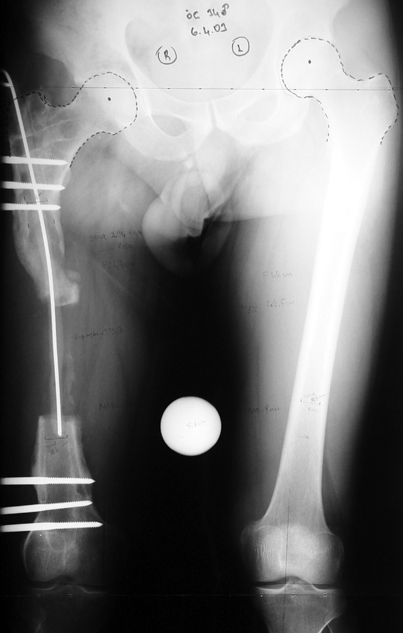

Case 1